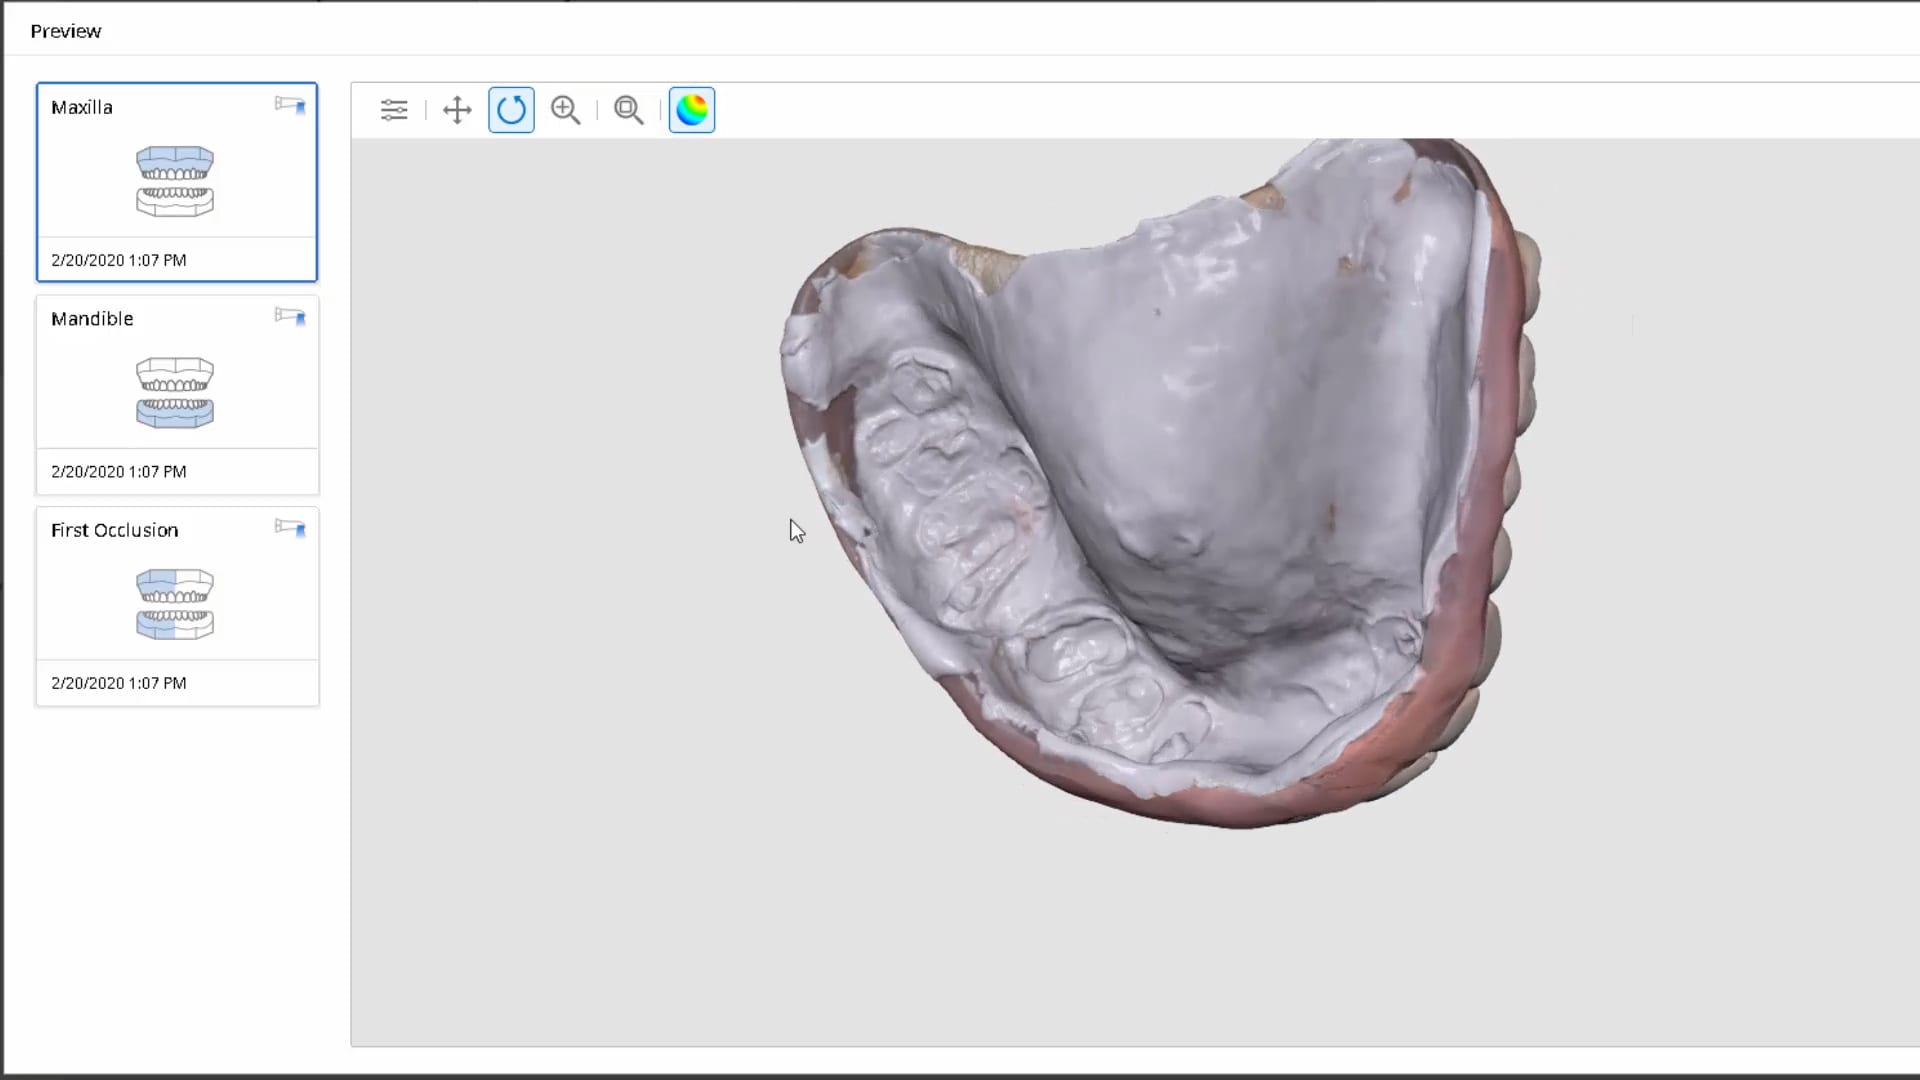

March 9, 2020Most manufacturers recommend that you start your imaging at the second molar area, which is the least practical area to start with. The tongue and the lip and saliva are […]